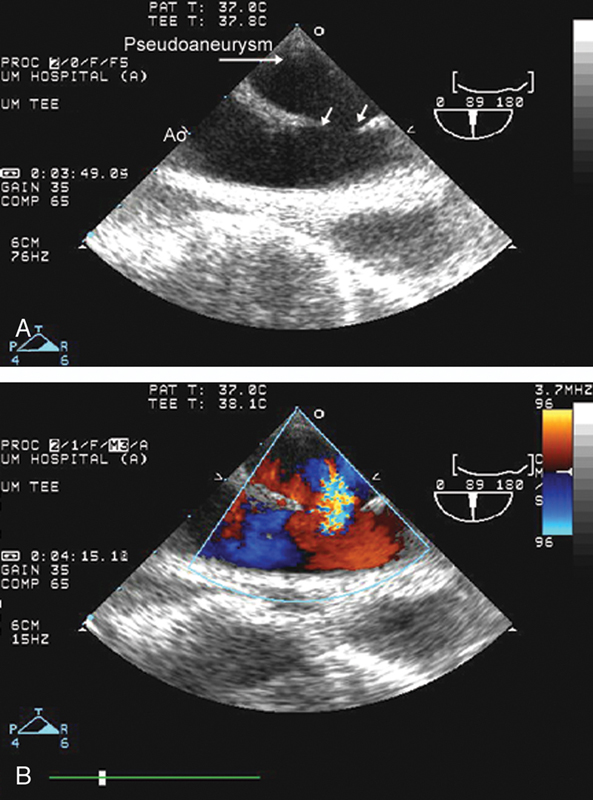

فحوصات تشخيصية لبعض امراض القلب والشرايين التاجية